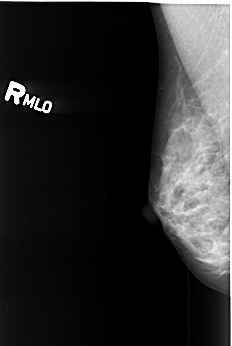

B_3418_1.RIGHT_MLO

RIGHT_MLO LINES 4144 PIXELS_PER_LINE 2784 BITS_PER_PIXEL 12 RESOLUTION 50 NON_OVERLAY